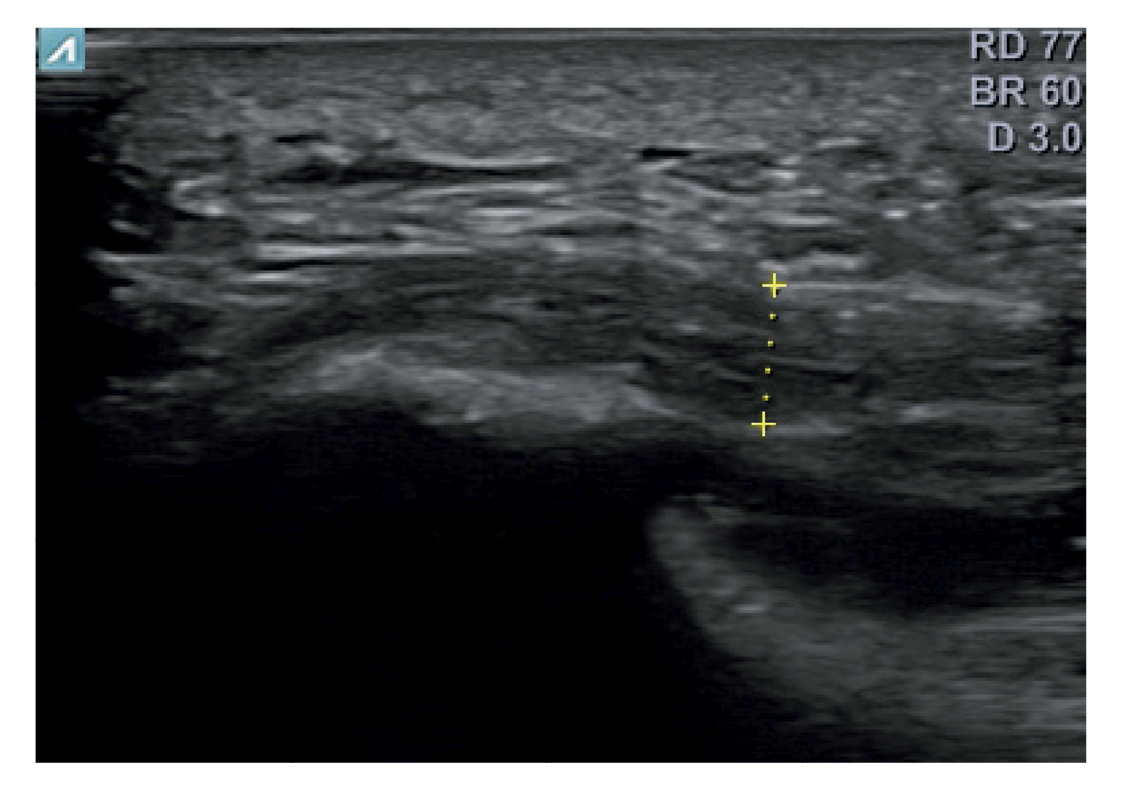

A todos los pacientes se les realizó una evaluación clínica y una evaluación ecográfica. La evaluación clínica se basó en una escala analógica visual (EVA) (13) (0-10) y el índice de función del pie (FFI) (14,15), que evalúa la función en una escala de 0 a 100. También se clasificó a los sujetos como sedentarios, activos o deportistas en función a su actividad física diaria, así como si era la primera vez que aparecía la enfermedad, era una recidiva o era crónica(16). También se evaluó el sexo, el peso y la talla, la presencia de vascularización en la fascia plantar visualizada con ecografía en el momento de la evaluación inicial y la forma biconvexa(17) o aplanada de la fascia plantar (Figura 1).

Figura 1. Fascia plantar con morfología normal a la izquierda y fascia plantar con morfología biconvexa a la derecha.

El diagnóstico se estableció en base a los síntomas y se confirmó mediante ecografía con equipo de alta resolución (Alpinion Ecube 9, ALPINION MEDICAL SYSTEMS Co., Ltd., República de Korea) con transductor lineal de 6 a 12 MHz (Figuras 2 y 3).

Figura 3. Área de medición del grosor de la fascia plantar. La línea punteada corresponde con la medición del grosor.